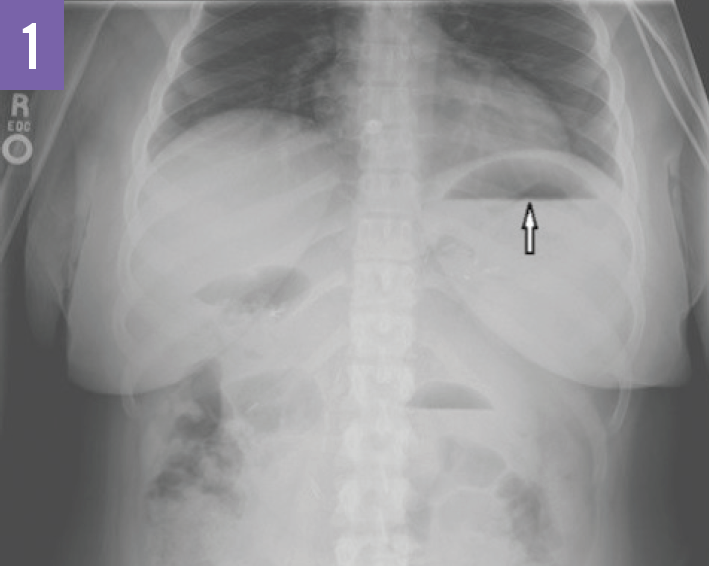

A Case of Pneumopericardium as a Late Complication of Gastric Bypass Gastric Sleeve On X Ray Laparoscopic sleeve gastrectomy is one of the most common bariatric procedures worldwide. It has recently gained in popularity. (left) radiograph shows an abnormal position of the gastric band , which has slipped inferiorly and rotated clockwise. Firstly, it is a restrictive procedure, meaning that it achieves weight loss by restricting. Sleeve gastrectomy is a bariatric surgical procedure involving resection of. Gastric Sleeve On X Ray.

Radiological Anatomy Stomach Stepwards Gastric Sleeve On X Ray (left) radiograph shows an abnormal position of the gastric band , which has slipped inferiorly and rotated clockwise. The connecting tubing has also migrated into a more rightward position than expected. It has recently gained in popularity. Firstly, it is a restrictive procedure, meaning that it achieves weight loss by restricting. Sleeve gastrectomy is a bariatric surgical procedure involving resection. Gastric Sleeve On X Ray.